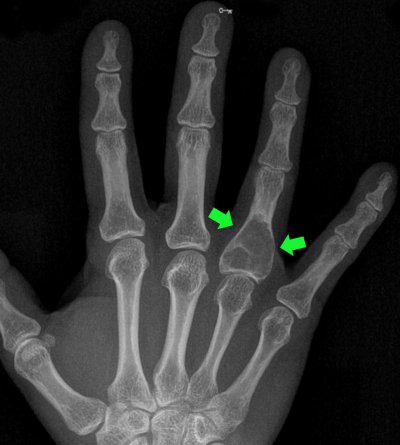

Tumors of cartilage origin can also develop inside the bone. Some of these are minor and require no treatment but follow-up. Others become larger and need to be treated with surgery. Enchondromas are bone tumors of cartilage origin. In other words, they are cartilage-like tumors that develop inside the bone.

Pic 8

Pic 9

There is also a low probability of malignant transformation. They can cause blunt pain from time to time. In this case, they must be surgically removed. Enchondromas are also the most common tumors of the hand bones. The patient may not be aware of this most of the time. It can develop inside the bone and make the bone walls, which we call the 'cortex', extremely thin. In this case, even with a very simple trauma, a fracture may occur in the bone. Sometimes there may be recovery without surgery, and sometimes there is an indication for surgery.